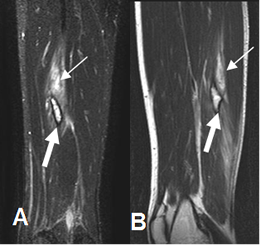

A: RM coronal en STIR y B: RM sagital en T2. Zona hiperintensa en ambas secuencias, sobre el músculo semimembranoso, con ruptura de algunas fibras, que corresponde a lesión muscular grado 2. (Flechas delgadas). En la parte mas inferior hay otra lesión hiperintensa rodeada por halo de hemosiderina, por lesión crónica. (Flechas gruesas).